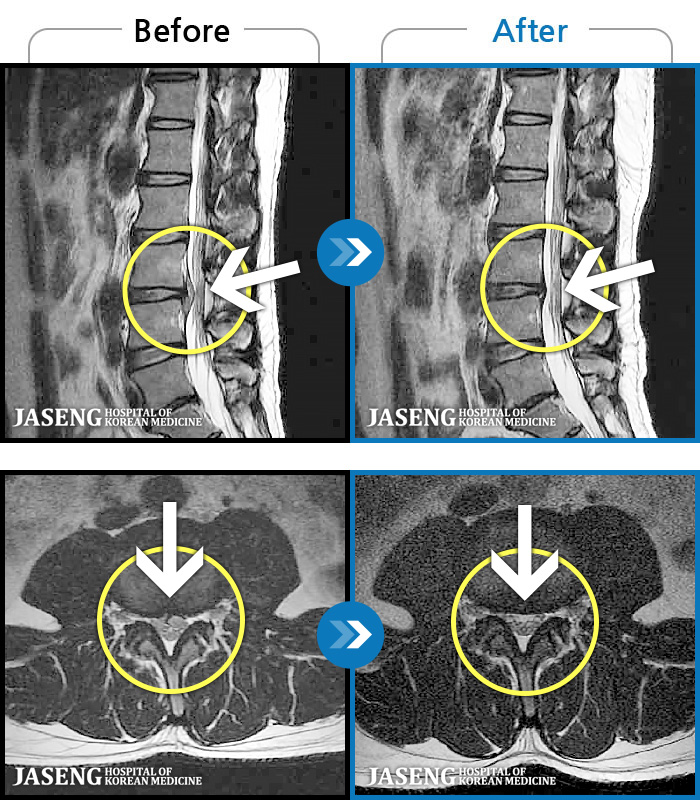

[뱸] 19.11.28~25.05.06